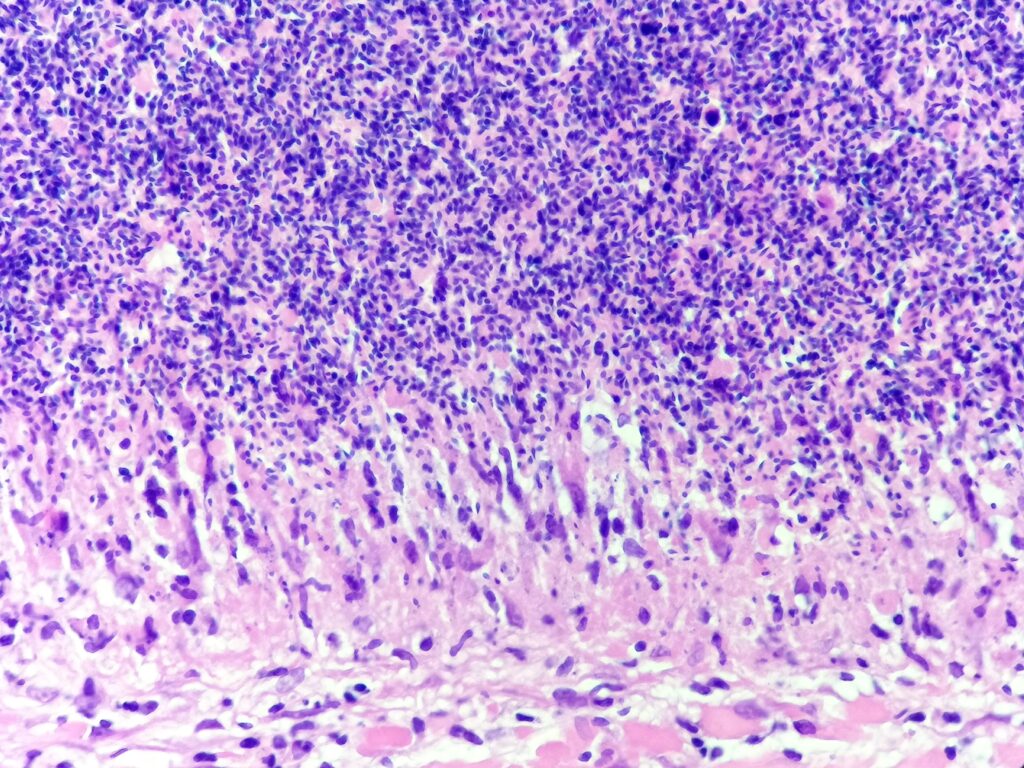

Obrazy mikroskopowe:

Cechy charakterystyczne:

- cienkościenna torbielowata struktura składająca się z tkanki łącznej (krzyżyk) wysłana jednowarstwowym nabłonkiem (czerwona strzałka) od kostkowego po walcowaty, z pojedynczymi komórkami rzęskowymi – torbiel nasienna patrz przypadek nr 105. SMP

- poza światłem zmiany obecne są plemniki (gwiazdka) z otaczającym odczynem z histiocytów (komórki o owalnym lub okrągłym jądrem komórkowym stosunkowo obfitej lekko kwasochłonnej cytoplazmie, niebieska strzałka), nieliczne limfocyty i komórki wielojądrowe (zielona strzałka) – ziarniniak

- brak komórek atypowych, martwicy centralnej, grzybów bądź innych mikroorganizmów

Ziarniniak nasienny (sperm granuloma)